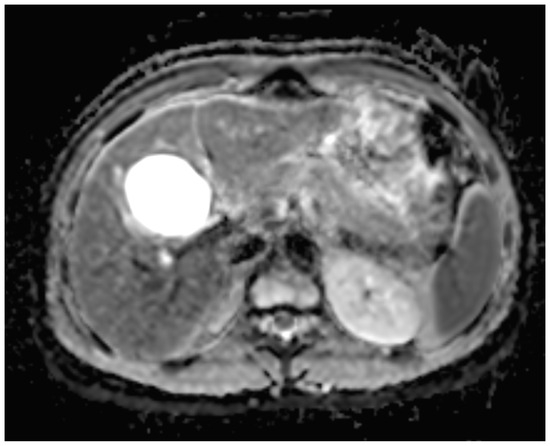

Six months later, a second ultrasound scan and a consecutive MRI scan to follow-up and control the success of the therapy were performed. The ultrasound revealed a decrease in the size of the cyst from 10 cm in maximal diameter to 9 cm and showed multiple circular septations, indicating an involuting cyst (Figure 7). In contrast to the preceding MRI scan, typical T2 hypointense membrane-like structures were observed within the lesion in T2WI. These represented most probably the floating membranes, the typical water-lily sign (Figure 8). T1WI (Figure 9) showed the cyst as a hypointense lesion, but the membranes could only be clearly observed in T2WI. Consecutively, the cyst was classified as WHO-CE3A.

Figure 8.

Second MRI scan: Axial T2W MRI scan, where floating membranes forming the water-lily sign after anthelmintic treatment, indicating stage WHO-C3a.

MR imaging clearly visualizes pericyst, matrix, and daughter cysts. The pericyst appears as a hypointense rim on both T1WI and T2WI due to its fibrous structure and the presence of calcifications. This is a specific feature of hydatid cysts, called the rim sign, mostly better visualized on T2WI [5]. The matrix represents hydatid-fluid-containing membranes of broken daughter vesicles, scolices, and hydatid sand [7]. The hydatid matrix appears hypointense on T1WI and significantly hyperintense on T2WI. However, the limitations of MRI scans are especially observed in stages CE4–CE5, as bigger calcifications are better observed on a CT scan. When daughter cysts are present, they are typically more hypointense than the matrix on T2WI, as observed in our case report [17] (Figure 1). If the membrane is separated, it can shift with movement, resembling a water lily floating on the surface of a pond, previously described as water-lily sign, which was seen in our case report as well [18] (Figure 8).